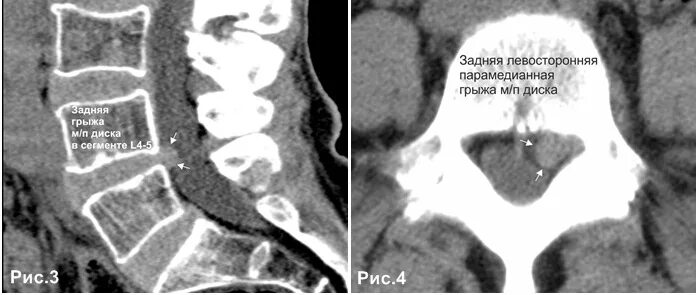

Медианно парамедианная протрузия диска